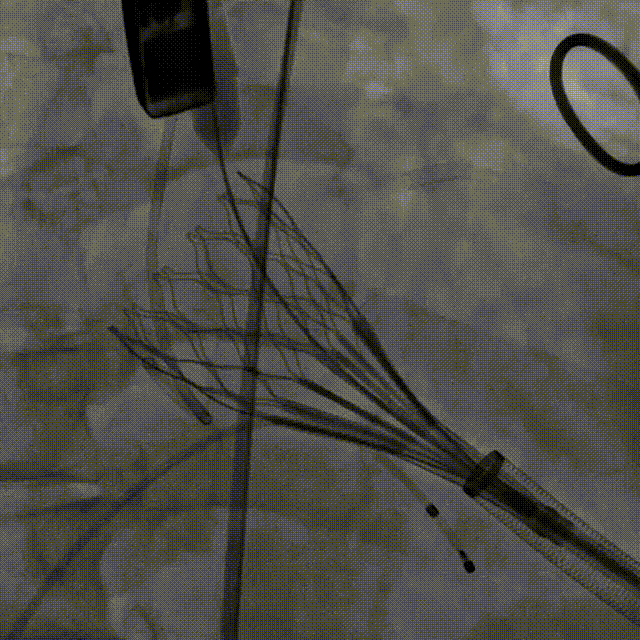

第二次释放

造影观察 瓣膜深度可

稳定脱钩,瓣膜无位移